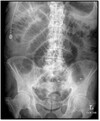

What pathology is seen here?

Small Bowel Obstruction